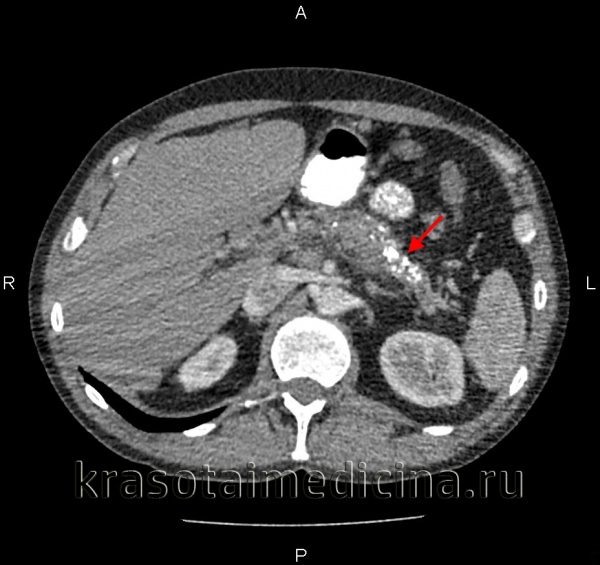

КТ органов брюшной полости. Множественные кальцинаты в области хвоста и тела поджелудочной железы (последствия множественных острых эпизодов панкреатита)